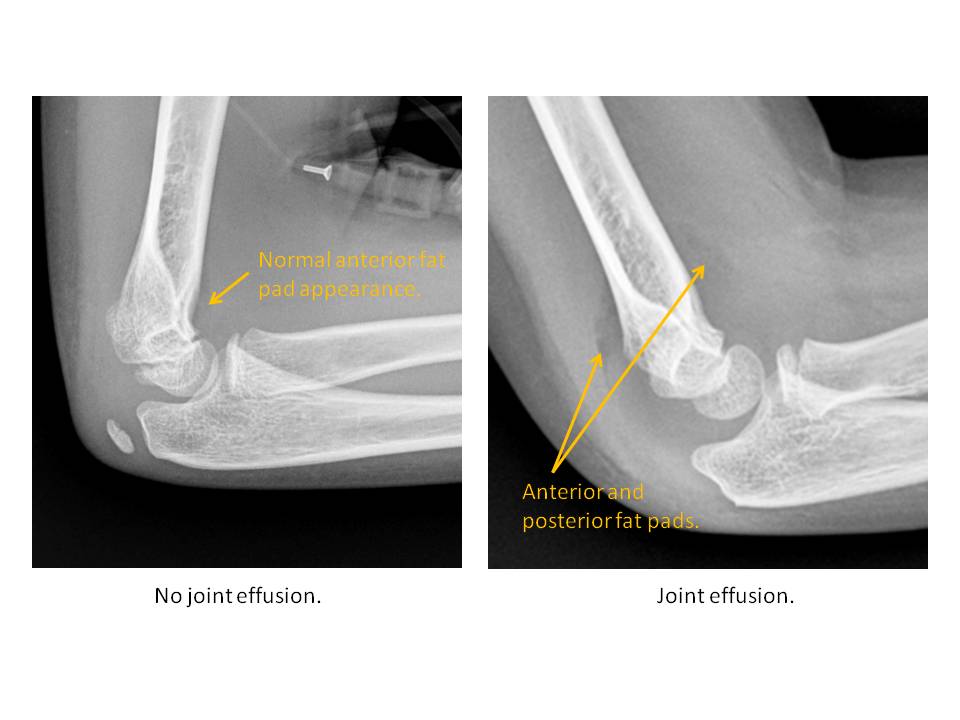

Section 1 Submit Findings Case090 Findings Image Quality The lateral radiograph is obliquely imaged. Yes No Soft Tissues A joint effusion is present. Yes No There is soft tissue edema/fullness overlying the olecranon process, overlying the lateral or medial epicondyles, or elsewhere about the elbow. Yes No There is soft tissue laceration or radiopaque foreign body. Yes No Alignment The anterior humeral line courses anterior or posterior to the middle third of the capitellar ossification center. Yes No A line drawn down the center of the radius does not pass through the center of the capitellum on all imaging planes. Yes No Ulnohumeral alignment is abnormal. Yes No Osseous The sequence of apophyseal ossification about the elbow is abnormal. Yes No The secondary ossification centers are abnormal in size, shape, or position. Yes No The physes are widened or irregular. Yes No The proximal radius is fractured. Yes No The coronoid process is fractured. Yes No The olecranon process is fractured. Yes No The medial or lateral humeral condyles are fractured. Yes No Based on the mechanism of visualized injuries, there are additional subtle abnormalities. Yes No A marrow replacing osseous lesion is present. Yes No